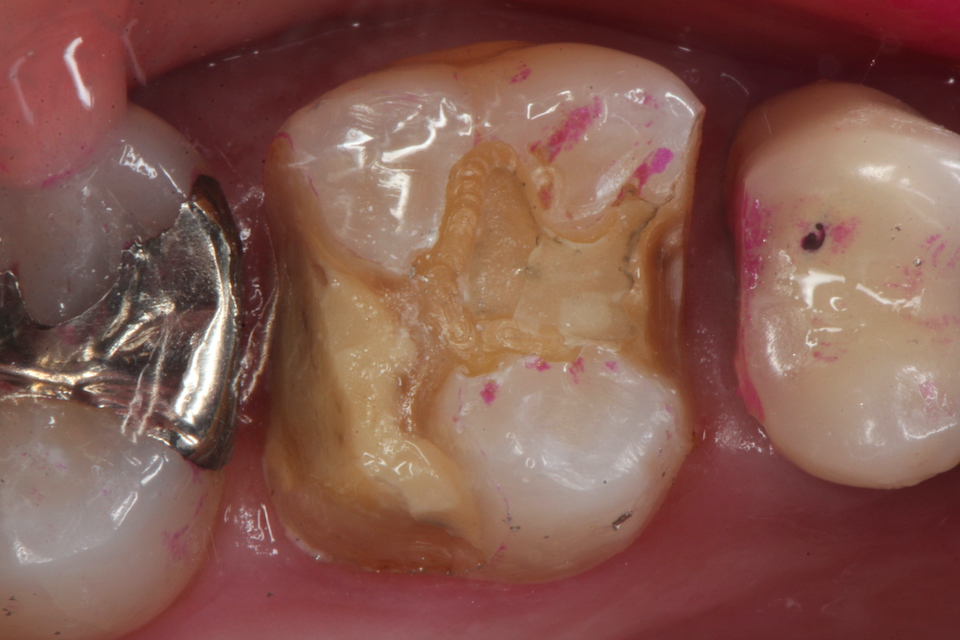

ブリッジ脱離で2次カリエス+Perでグラグ… 2025.11.01

ブリッジ脱離で2次カリエス+Perでグラグ… 2025.10.31